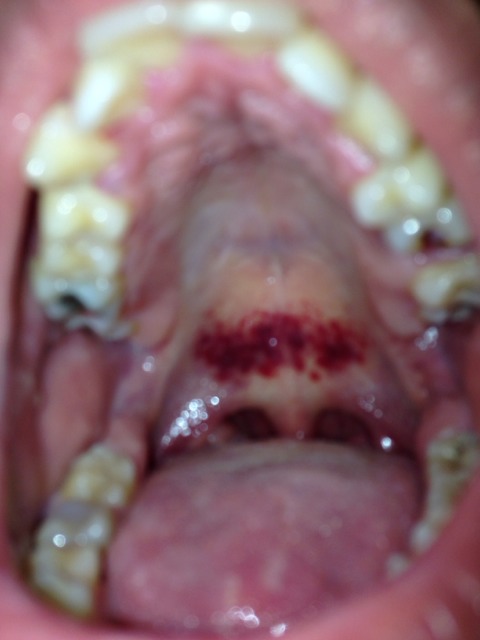

Tache Rouge Sur Le Palais Un Signe De Cancer

Tache Rouge Sur Le Palais Cancer S Forum Sante

Le Syndrome De La Fellation Vigoureuse Realites Biomedicales

Les Symptomes Et Causes Du Cancer Du Palais

Tache Rouge Palais Journal Des Femmes

Tache Rouge Au Palais Est Ce Un Aphte